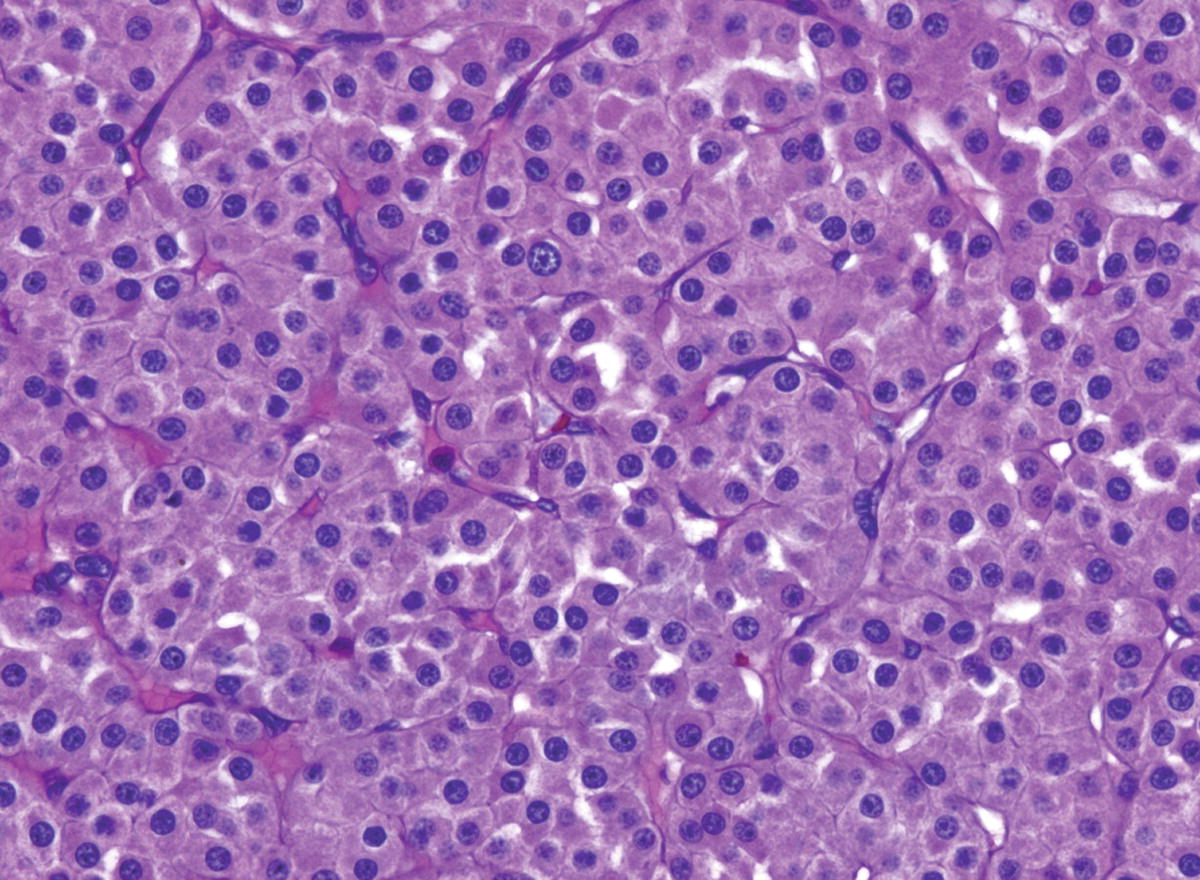

Irregular infiltrating edges wilms tumor. Resembles leiomyoma with whorled cut surface. Kidney pathology pathology in outline format with mouse over histology previews. Congenital mesoblastic nephroma although rare is the most common renal neoplasm in the first months of life.

On ct images visualizing the symmetric excretion of contrast material by the remaining functioning renal parenchyma helps to differentiate mcrt from multicystic dysplastic kidney. This neoplasm is generally non aggressive and amenable to surgical removal. In rare cases the tumor may be seen in the kidneys a condition known as cellular congenital mesoblastic nephroma cmn surgically excised tumors are known to return.